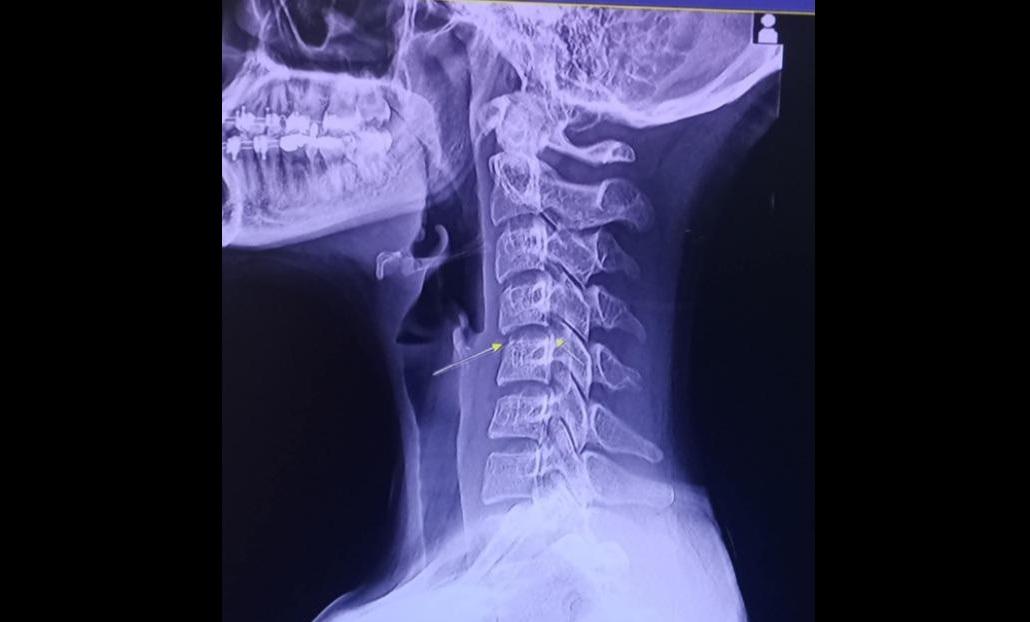

31歲的Phing Chayada因lock頸導致神經受損,最後死於與血管感染和腦部腫脹有關的併發症。(互聯網)

做泰式按摩要小心。泰國一名女歌手因肩膀酸痛去按摩,按摩師幫她「扭轉頸部」(俗稱lock頸)後感不適,其後惡化至半身癱瘓,一個月後更不幸逝世,終年31歲。當地醫生促請按摩師不要為客人做「lock頸」,避免他們受傷。

醫生診斷發現她的頸椎早已受傷,在按摩後導致神經受損,不幸演變成半身癱瘓,只能躺在床上。泰國傳媒指,Chayada最後死於與血管感染和腦部腫脹有關的併發症。